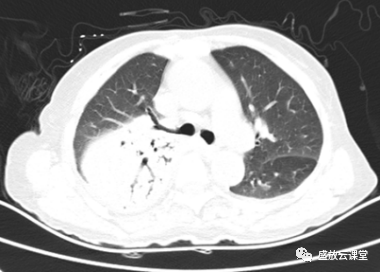

【病例】肺淋巴瘤(MALT)一例CT影像-4

【病例】肺淋巴瘤(MALT)一例CT影像-5